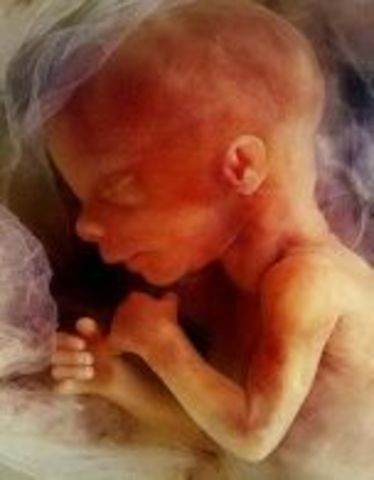

• Week 14

Week 14

The fetus in now 3.5 inches long. The face is starting to become more visible and the baby is peeing. Bones are getting stronger and harder and hair is starting to develop.

• Week 15

Week 15

The baby is 4 inches long. The legs and arms are growing longer than the head. The skin is very thin and the bone marrow is developing throughout the skeletal sysem.